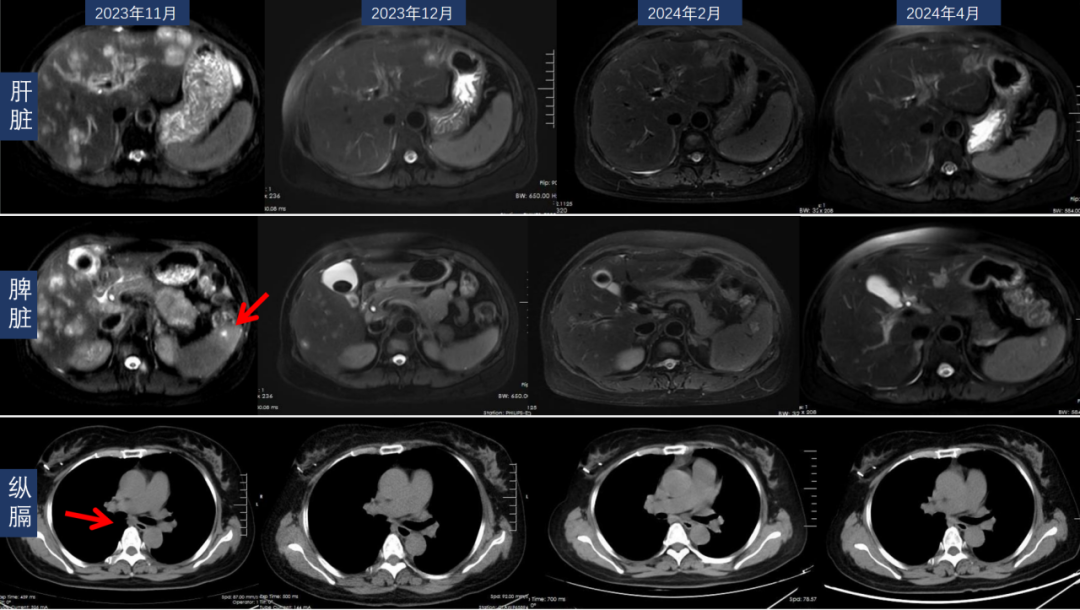

目前(截至2024年5月)患者已完成8个周期的戈沙妥珠单抗治疗。2023年12月、2024年2月及4月复查CT及MR如下图所示,肝、脾病灶和纵隔淋巴结、小脑转移病灶均有退缩、缓解。

△2023年11月以来复查胸腹部CT转移灶变化

△2023年12月以来复查头颅MR转移灶变化

疗效评价:最佳疗效PR;PFS2未达到(随访>6个月)。